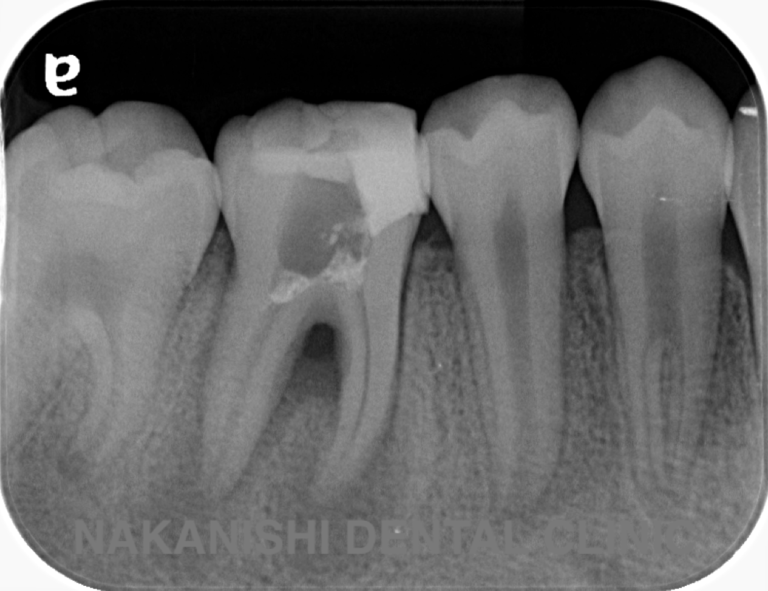

case 1.

治療前

治療後

| 主訴 | 右下歯ぐきの腫れ。 他院で抜歯と言われ、セカンドオピニオン希望でご来院。 |

|---|---|

| 治療期間 | 1か月 |

| 治療費 | 約2万円 |

| 治療内容 | ラバーダム、マイクロスコープ下にて根管治療を施術。歯肉腫脹と疼痛は消失し補綴物を作製し治療終了。治療後のレントゲン写真は2年後のものです。 |

| 治療のリスク | マイクロスコープやCTを使用し、可能な限り精密な根管治療を行っていますが、歯根の形態や病変の大きさ、過去の治療履歴などにより、治癒が得られない場合があります。 また、治療後に再感染や歯根破折が生じることもあり、その場合は再治療や抜歯が必要となることがあります。 治療結果には個人差があり、すべての症例で同様の経過を保証するものではありません。 |